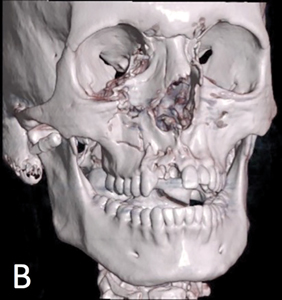

The Role of the Dentist in Recognizing Orbital and Ocular Trauma

Orbital and Ocular Trauma

Introduction General dentists and dental specialists alike are often called upon by Emergency Department (ED) physicians to assess patients with dental injuries and concomitant maxillofacial trauma. Whether the assessment occurs in the ED, the hospital ward, or the private dental clinic, a full examination of the oral and maxillofacial structures is required to identify all … Read more